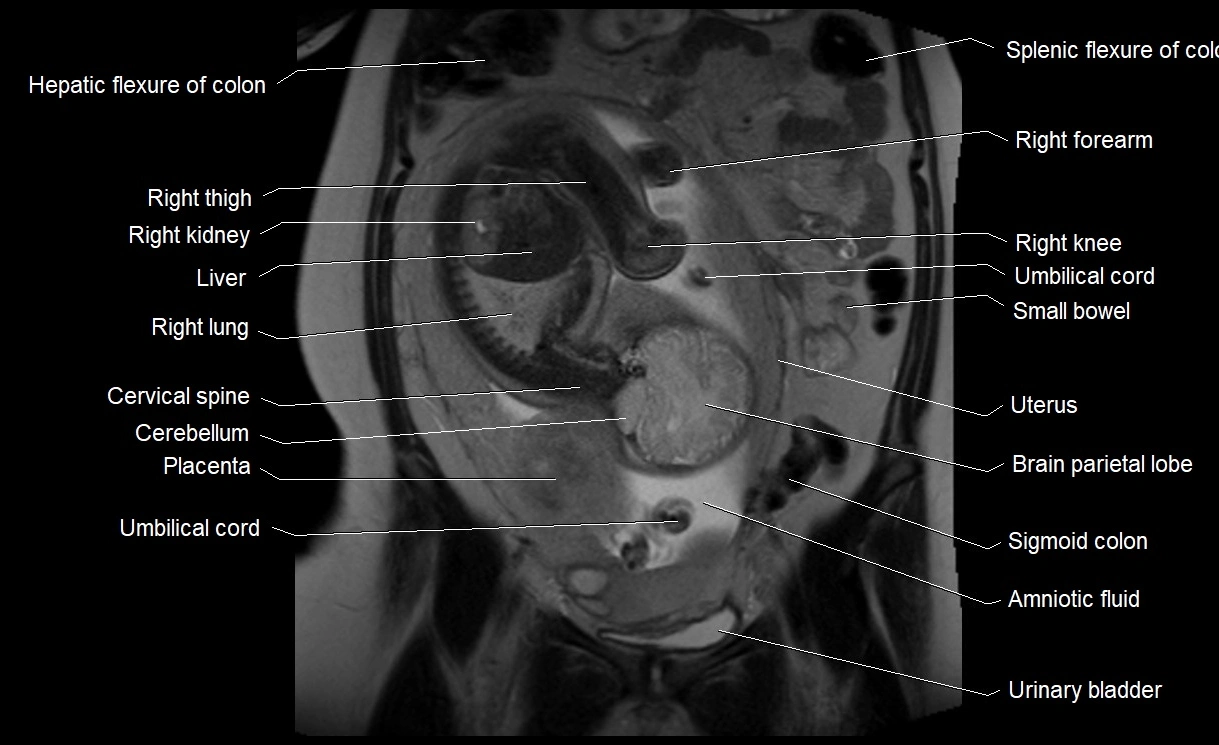

• Imaging relevance: MRI used for fetal visualization and assessing oligohydramnios/polyhydramnios when ultrasound is inconclusive

MRI Appearance

T2 HASTE (T2 GRE):

• Amniotic fluid shows very bright hyperintense signal

• Provides natural contrast against fetus and placenta

• Small particles (vernix) may appear as scattered hypointense foci within bright fluid

T1 GRE:

• Amniotic fluid shows low signal intensity (dark)

• Hemorrhage, infection, or proteinaceous content may cause focal or diffuse high signal intensity

MRI image

image